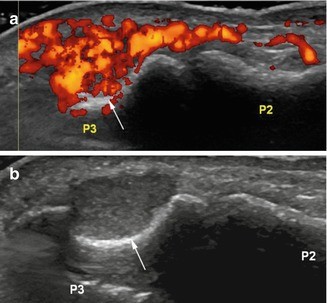

Glomus tumor of the nail bed. (a) Ultrasound. (b) Power Doppler image. (a) Ultrasound images show an isoechogenic mass eroding the underlying distal phalanx (P3) (arrow). The lesion is markedly hypervascular (b) on power Doppler image

Glomus tumor of the nail bed. Axial T2-weighted MR image with fat suppression shows a 2 mm markedly hyperintense lesion of the nail bed